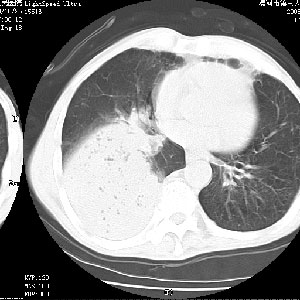

m 老年 发烧、呼吸困难,慢支、肺气肿多年;记的那次是下午大概17:38做的,晚上窒息死亡。

上面的层面就慢性支气管炎肺气肿、肺大泡,别的没有什么、也就不传了。

当时我怀疑:1、阻塞性肺不张早期 2、肺脓肿早期,望老师们发表意见

应该是脓胸的表现,右下肺气管阻塞考虑为痰栓.

你怀疑的有道理,慢支、肺气肿、肺打泡是有了,右下肺的病变有待商议;

首先考虑右下肺炎症并不张,不除外早期肺泡癌改变

病灶边缘清---多个含气小腔---近端未见通畅气管影-----支持-----慢性肺脓肿继发阻塞性肺不张

阻塞性肺不张原因-----脓液未排出

1、右侧脓胸;2、copd;

3、细支气管肺泡癌可以排除,病变以斜裂为界,呈大片状高密度影,内可见多发小气泡,表明有产气杆菌感染所致,内无明显的支气管“枯树枝征”表现,再结合其临床改变(细支气管肺泡癌临表表现重、影像表现轻)所以不符合细支气管肺泡癌(炎症型)的改变。